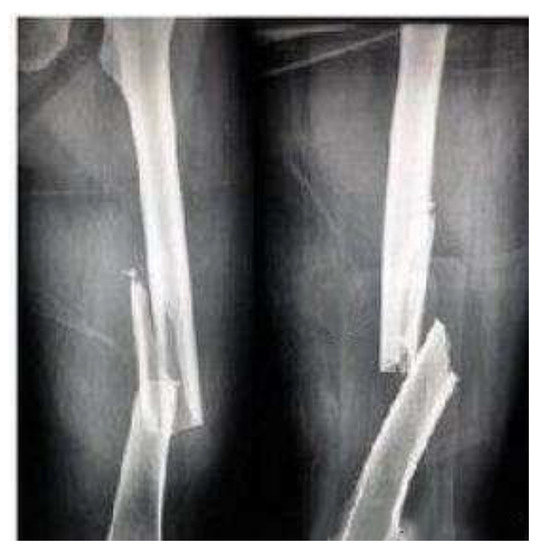

3.1. Acquisition of Patient Position Data